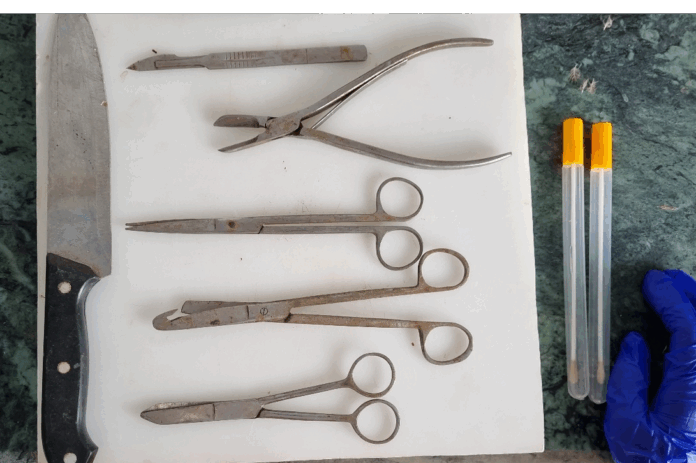

Equipment for postmortem (Fig.1):

- Small and large straight scissors with pointed as well as blunt ends.

- Curved scissors.

- Small and large knives.

- Scalpel or blade.

- Bone cutter and a saw.

- Small and large forceps.

- Tooth forceps.

- Hand lens.

- Hand gloves – rubber or latex.

- Bunsen burner or spirit lamp or stove.

- Syringes and needles.

- Spirit or alcohol.

- Cotton and cotton swabs. Sterile swabs, vials, petri dishes and test tubes. (swab for bacteria and virus are different)

- Pasteur pipettes and rubber bulbs.

- Fixatives like 10% formalin, formol saline or netural formalin.

- Clean glass slides and coverslips.

- Different staining sets and stains like Gram’s, Ziehl – Neelsen, Giemsa and Wright’s stain.

- Normal saline and glycerine saline.

- Small and large trays.

- Matches and torch.

- Disinfectants like dettol, savlon, phenol etc.

- Insecticides or electric flytrap for controlling fly population.

Figure 1. Post mortem equipment/materials